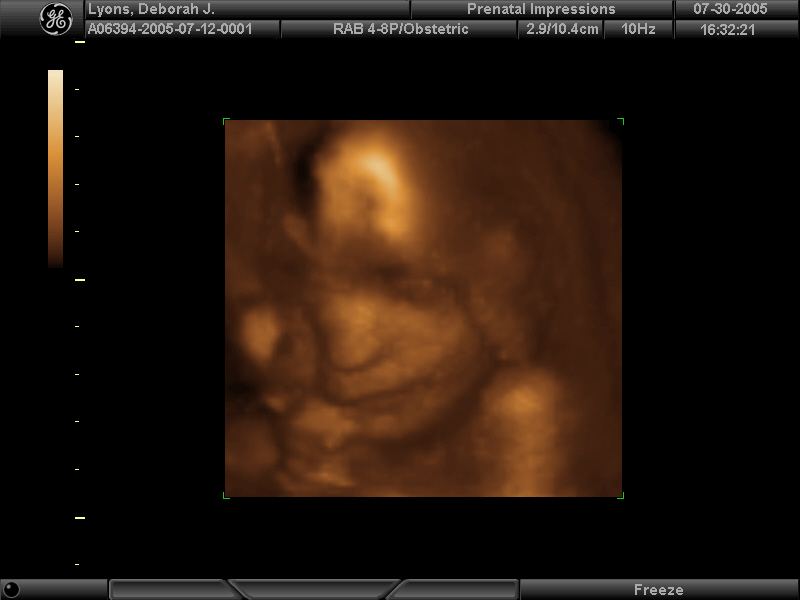

3d -- baby_lyons__36.jpg